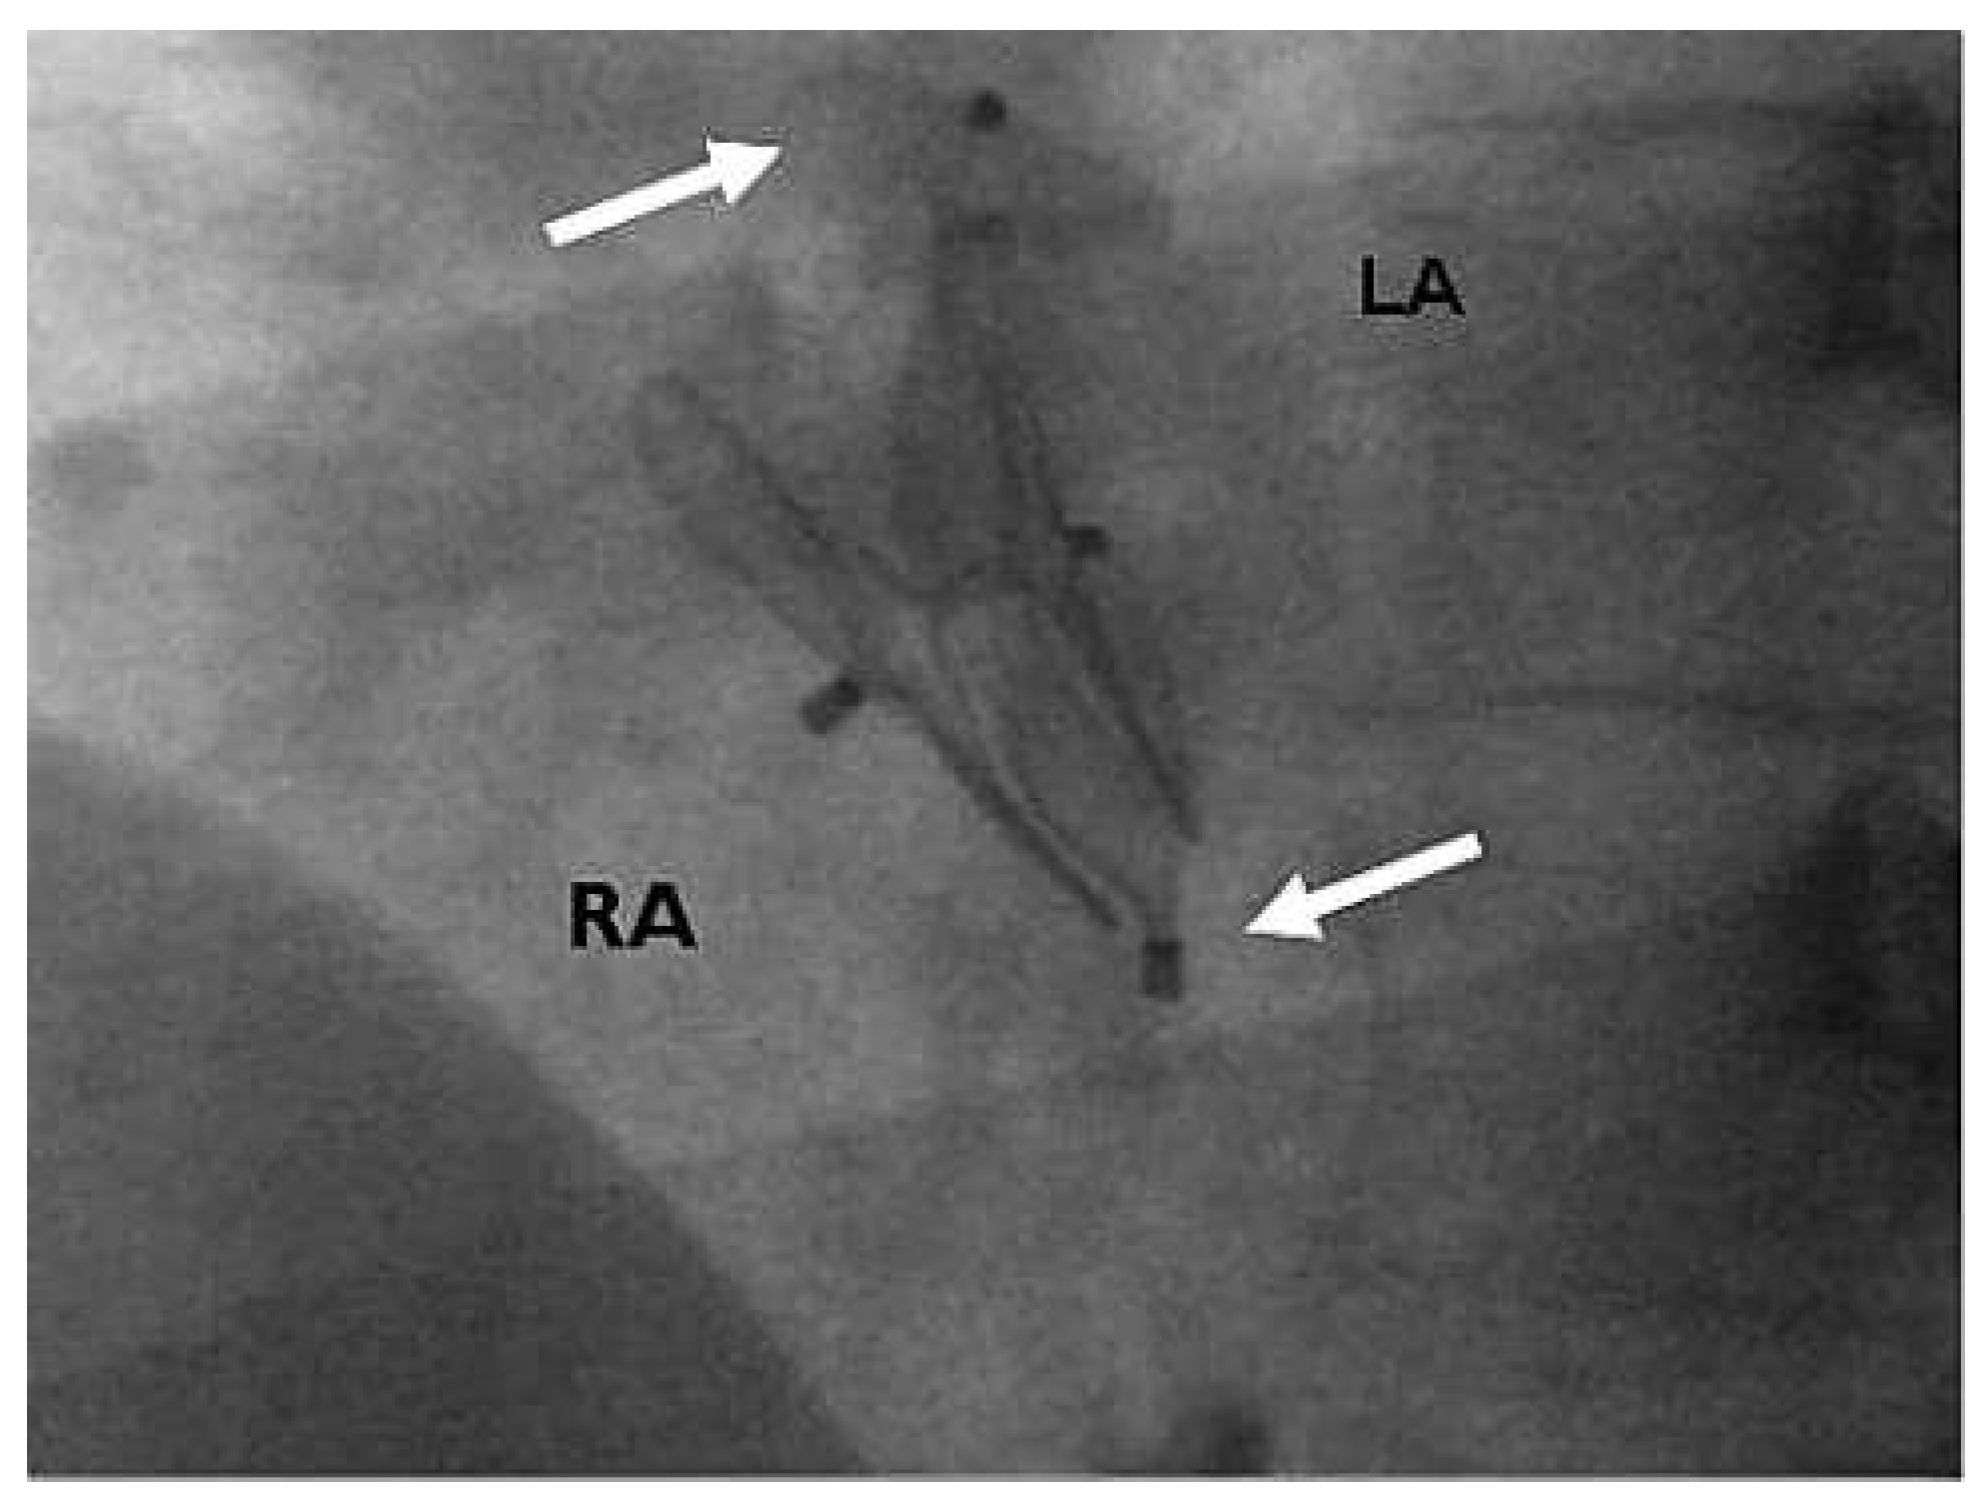

Figure 3. Placement of a second 25-mm Amplatzer PFO Occluder (arrows), with the right disk sandwiched like a banana by the initial. 30-mm Amplatzer PFO Occluder. LA = left atrium; RA = right atrium.

Six months later, follow-up contrast TOE documented a residual shunt grade III (Figure 2). Using the same technique, a second 25-mm APFO was implanted (Figure 3). Contrast TTE performed the next day did not detect any residual shunt. Clopidogrel 75 mg was again prescribed for 1 month and acetylsalicylic acid 100 mg for 5 months.